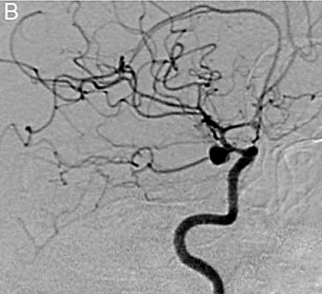

Paciente, 38 anos, admitida em pronto socorro com queixa de cefaleia súbita, associada a visão dupla e vômitos. Submetida a tomografia de crânio sem contraste com a presença de hemorragia subaracnoidea. Encaminhada para o serviço de hemodinâmica para angiografia de vasos cerebrais (figura 5).

Figura 5 Arteriografia cerebral

A respeito a etiologia da HSA, assinale a alternativa correta.